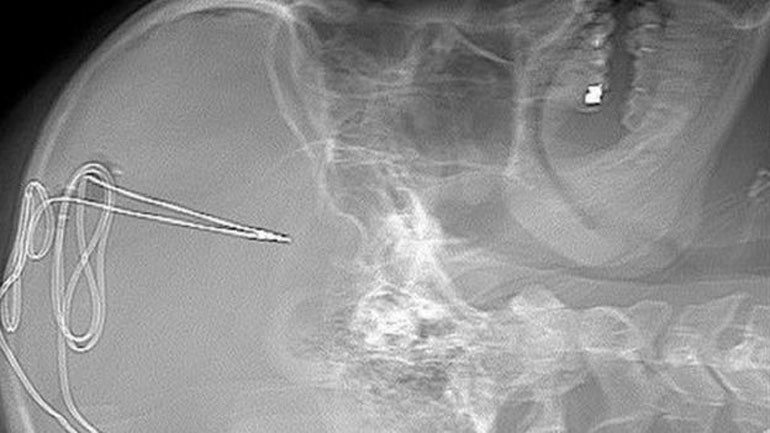

Процедура начинается с серии сканирований головного мозга. Затем следует операция, в ходе которой врачи делают маленькое отверстие в черепе, чтобы внедрить крошечный электрод диаметром 1 мм в конкретную область мозга, регулирующую импульсы, связанные с зависимостью и самоконтролем. Под ключицей располагается батарея для обеспечения работоспособности устройства. В дальнейшем группа врачей, психологов и экспертов по наркологии будет дистанционно контролировать активность мозга, чтобы увидеть, исчезнет ли тяга к употреблению наркотиков.